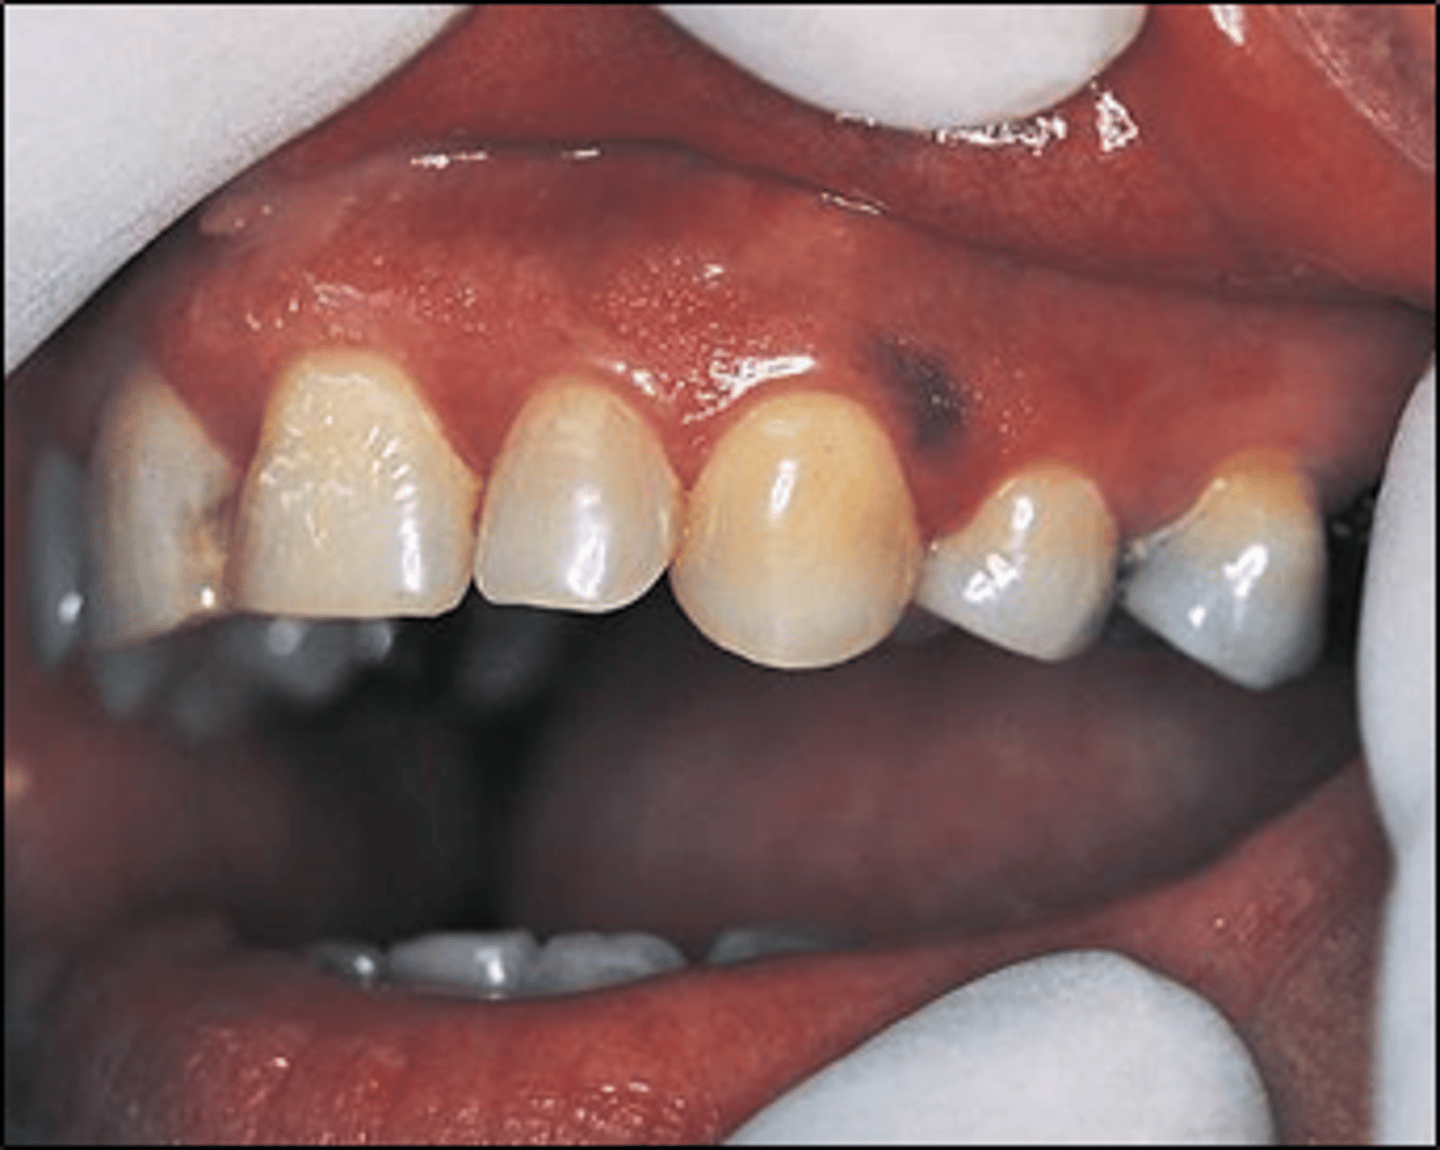

What is an amalgam tattoo?

presence/history of amalgam restoration

⢠can see on X-ray